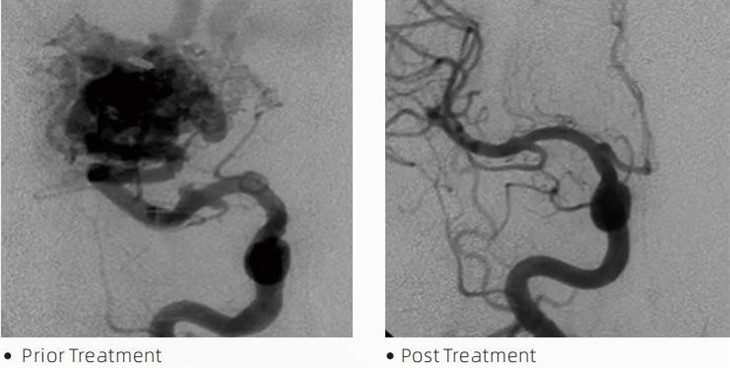

LavaTMembolisk lim er et medicinsk udstyr, der bruges af interventionelle neuroradiologer under minimalt invasive procedurer til at behandle tilstande som cerebrale aneurismer, arteriovenøse misdannelser og tumorer. Lava embolisk lim tilbyder adskillige fordele for både læger og patienter med hensyn til sikkerhed, brugervenlighed og effektivitet. Lava er i stand til at forsegle blodkar hurtigt og effektivt. Processen involverer at sprøjte limen direkte ind i målbeholderen, hvor den polymeriserer og hærder til en støbelignende masse, der fylder aneurismen eller misdannelsen. Derefter afbryder det effektivt blodtilførslen til læsionen, hvilket forhindrer den i at briste og reducerer risikoen for permanent skade eller slagtilfælde. Lava omfatter Lava-12, Lava-18 og Lava-34. Hver formulering er designet til at imødekomme specifikke kliniske behov. Lava-18 er standardformulering til generel brug. Lava-34 er højviskositetslim til højflowbeholdere. Mens Lava-12 har en lavere viskositet og er mere flydende, hvilket giver mulighed for distale mikrokar. Med disse muligheder kan interventionelle neuroradiologer vælge de passende Lava-formuleringer for at sikre optimale resultater. En af de mest bemærkelsesværdige egenskaber ved Lava er dens ikke-klæbende egenskaber. Dette stof er specielt formuleret til at forblive stabilt, indtil det når målområdet. Denne egenskab betyder, at Lava-embolisk lim nøjagtigt kan placeres i arterien og forblive der uden at klæbe eller binde til det omgivende væv.